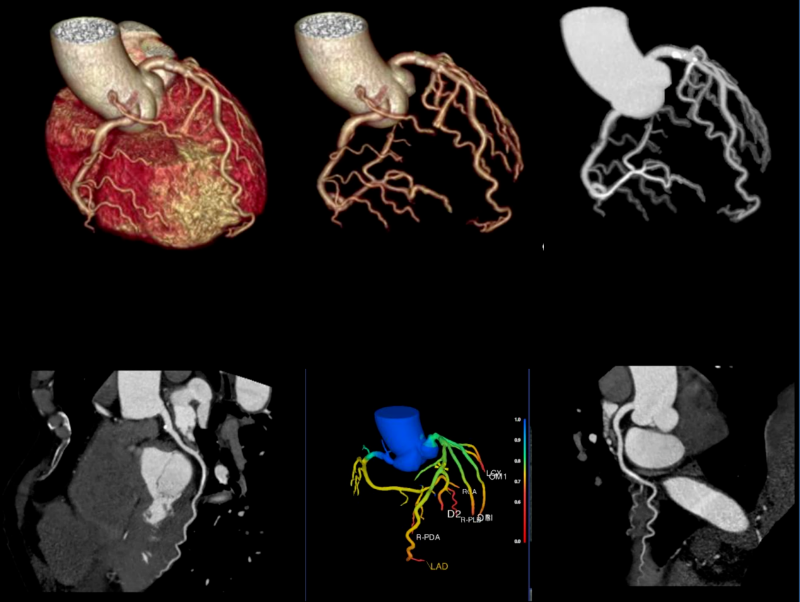

该设备集 “超高清成像、低剂量防护、极速扫描”于一体,将为辖区居民提供更精准、更安全、更便捷的诊断服务,标志着石岩人民医院在医学影像领域的诊疗水平迈入新阶段。 作为临床诊断的 “眼睛”,ANATOM X980的三大核心功能,直击患者就医痛点与临床诊断需求。 人性化设计与智能定位系统 ANATOM X980配备80厘米宽大机架孔径,结合舒缓氛围灯光,有效缓解患者检查时的紧张情绪。 设备搭载四块大尺寸高清触控屏,方便技师多角度掌握患者信息与设备状态,并可通过按键与无线遥控实现灵活摆位,大幅降低操作负荷,提升检查效率。 利用深度双目视觉认知系统,采用深度学习方式,赋予设备认知能力和行为,使系统能智能识别人体多个定位点,并在智能触屏终端上显示扫描部位,同时还能够自动识别拟扫描部位的等中心位置,实现精准化、智能化的患者摆位。 宽体探测器与极速扫描能力 依托16厘米宽体探测器结合0.25s的扫描速度,可实现全器官一站式扫描。 ▲ 心脏冠脉、主动脉、肺动脉联合扫描 通过AccuGating门控触发技术和 Adose mA电流调制技术和全新的算法、领先的AI成像技术手段,结合一键冠脉提取及分析、IVUS 模拟血管内超声、斑块分析、心功能分析、钙化积分分析、血管内窥镜、CT-FFR 技术,为患者带来了高成功率、高舒适度的单心跳(One-beat)心脏冠脉(CCTA)检查体验。 ▲ 心率103bpm 得益于一次单圈旋转最大16cm的覆盖范围,结合0.25s 的极快速度和安科独创的4D图像重建技术,在充分保证整个器官的各个位置数据的同时、同源、同向的条件下,实现了自由呼吸模式的肺部检查,为幼童、意识不清等患者肺部检查提供了最佳检查方式,为分析结果和治疗决策的准确性提供了保证。 高清影像与低剂量技术 ANATOM X980采用了基于深度学习技术的Artist 高保真图像降噪算法来对低剂量图像进行优化和处理。 与其他的算法相比,Artist 可以实现更彻底的噪声与图像信号分离,并确保在处理过程中图像细节信息不丢失,进而获得低剂量下高分辨的临床影像。 灌注扫描的剂量问题一直是临床中的老大难问题。ANATOM X980的超低mA采集及Artist还可在脑卒中解决方案中,可确保低剂量下获得精准的灌注数据。 此外,ANATOM X980还有其它几大独具特色的功能。 1.AI超分辨薄层重建技术(ASR) ANATOM X980搭载基于AI技术的高分辨率薄层图像重建技术(ASR=AI Super Resolution reconstruction),该技术利用神经网络处理单元通过深度学习的方式,对带有伪影的混叠投影数据进行伪影校正和重建,可显著降低混叠伪影,提高 CT 图像的分辨率,获得高分辨 0.3125mm 的超薄层图像,从而提高临床诊断准确性。 2.AccuImage 2048×2048显微成像 将图像数据量提高 16 倍,可显示和观察更多的病变影像细节。 3.AccuSpiral能谱成像 基于AI迭代重建与能谱解析技术,可定量分析组织成分,辅助肿瘤良恶性鉴别、结石成分分析及出血定位,为临床提供形态与功能融合的多维度信息。 目前,ANATOM X980 已在石岩人民医院影像科正式投入使用,从常规体检到复杂病症诊断,从成人检查到儿童诊疗,全方位满足临床需求。 石岩人民医院将以这台 “精准诊断利器” 为依托,持续提升诊疗能力,让居民在家门口即能享受到高质量医疗服务,用科技守护每一位居民的健康! 咨询电话 0755-27609000转0121 石岩人民医院放射科 石岩医院放射科现有医护42人,其中主任医师1名,副主任医师5名,中级职称24名,初级9名,助理技师、岗培各2名。 设备由数字化DR、CT、MR、DSA和骨密度仪等组成。中心设备齐全,拥有世界上先进的1.5T磁共振(MR)一台;螺旋CT3台(包括安科256排512层CT1台、安科64排128层CT1台、安科32排CT1台)。 数字减影血管造影机(DSA)1台;数字胃肠机1台;数字化DR和移动DR共6台;并配有现代化的PACS、HIS、肺结节和心脑血管AI辅助后处理诊断系统。 审核|梁雄 责编|马章林 审校|张永东 图文|郭文霞 编辑|冯丽萍 校对|吴曼莉